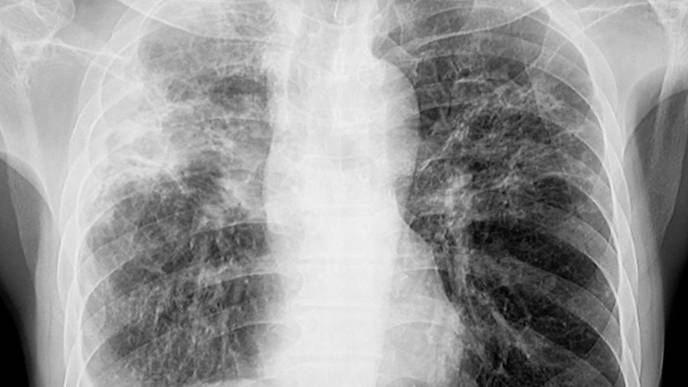

ILD in patients with SSc is usually characterized by bilateral, ground-glass opacities, lower-lobe predominant reticulations, and occasionally honeycombing when seen on high-resolution computed tomography (HRCT). Because mild ILD patients may not exhibit any symptoms in the early stages of the illness, they might not have pulmonary function tests or diagnostic radiography done until they start to express symptoms like dyspnea upon exercise and a persistent cough. On late presentations of ILD, nothing is clear. Thus, the team led by Sabrina Hoa carried out this investigation to describe the incidence, risk factors, and consequences of late-onset SSc-ILD.